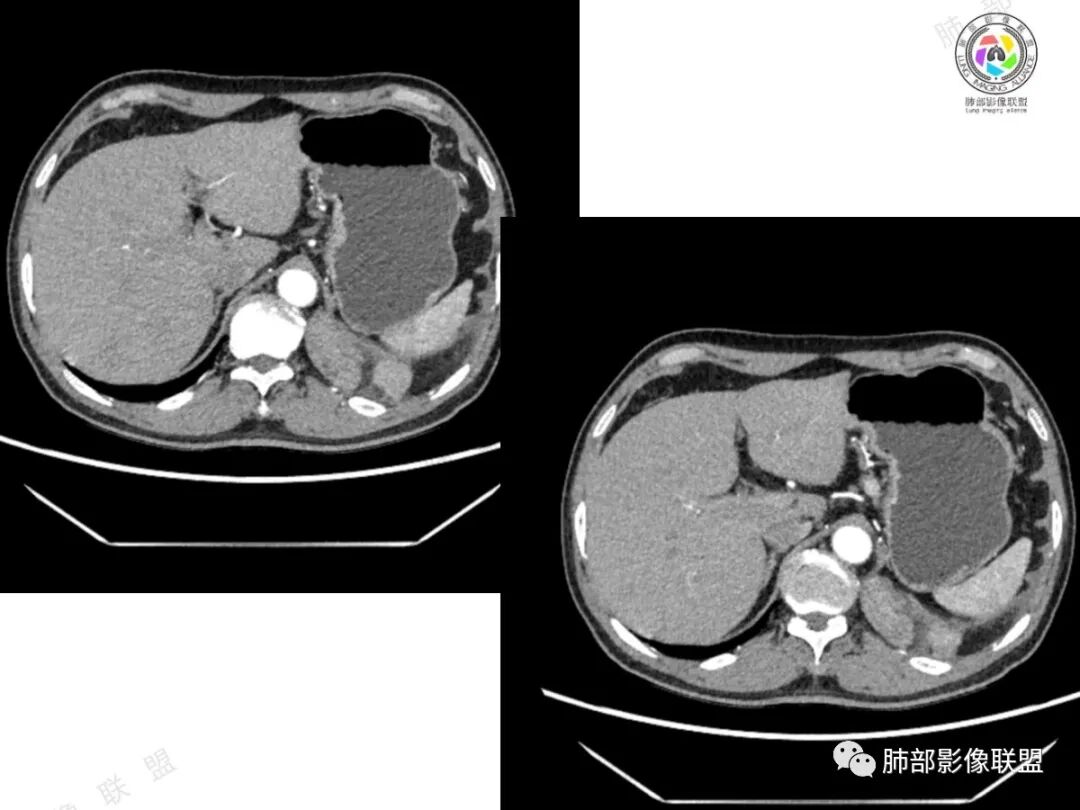

2、影像所见:左侧纵隔紧贴心包铸型生长巨大混杂密度肿块,边界清楚,临近结构受推挤移位,无明显外侵征象。肿块自主动脉弓旁一直顺延到至膈顶,呈“垂乳征”。病灶脂肪成分居多,斑片状、结节状及团块状实性密度成分散落其中,呈地图样分布,实性成分偶见低密度线样分隔,未见明确钙化影。增强扫描实性成分呈延迟明显强化,并见强化血管影。纵隔内有肿大淋巴结,未见胸腔积液,肺内及胸膜未见转移性病灶。

①脂肪肉瘤:本例含较多脂肪组织,需考虑分化成熟型脂肪肉瘤(高分化型)的可能,其好发于前中纵隔的下部及心膈角区,肿块常大,偏于一侧,可有分叶,包膜可完整,与周围组织器官界限清楚。以脂肪密度为主的肿块,增强后仅见间隔或实性部分轻微强化。而本例实性成分过多,且实性病灶强化较明显,与高分化型脂肪肉瘤表现矛盾。

4、疑惑:本例临床病史与影像表现,似乎单纯用一元论不足以解释全部,故要考虑到有无二元共存的可能性。

结果:碰撞瘤

胸腺瘤伴畸胎瘤